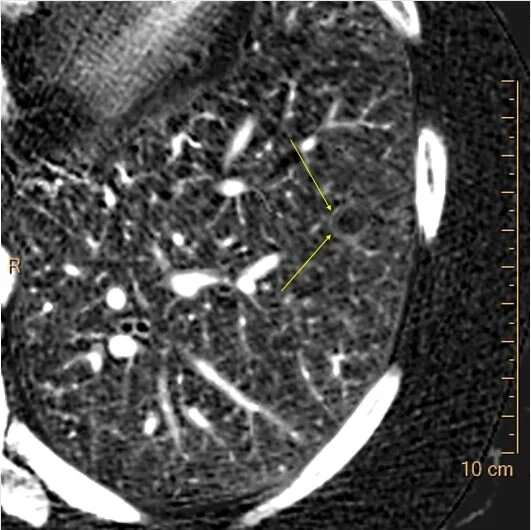

Iodine map shows no uptake in this nodule. Notice ring of iodine uptake around nodule (yellow arrows), something I see commonly in benign nodules.